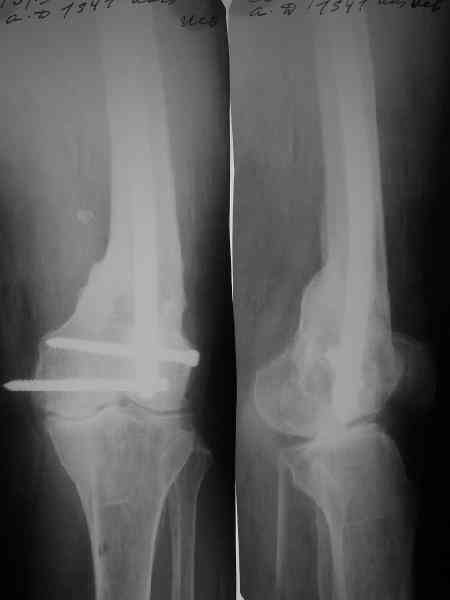

Пример подобного ложного сустава в приложении.

На сегодня есть имплантаты с куда более продвинутой дистальной фиксацией.

Выглядит красиво. А движения в колене какие были на столе?